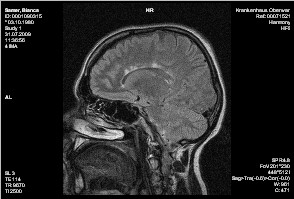

Cerebrum:

Es finden sich multiple, im Balken und periventriculär liegende rund-ovale und fingerförmige T2w hyperintense Glialäsionen, von ihrer Form vereinbar mit Enc. diss. Weiters Glialäsionen um die Hinterhörnder der Seitenventrikel und um das li. Temporalhorn. Die Läsionen zeignen kein Kontrastmittelenhancement.

Keine Ödemzonen. Normal weiter Liquorräume.